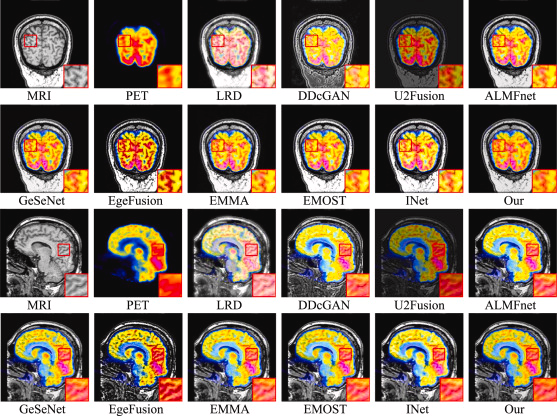

The equivalent results for the MRI-PET fusion data are shown below:

Visualization of two pairs of fused images from the MRI-PET dataset for LWNet and comparison methods